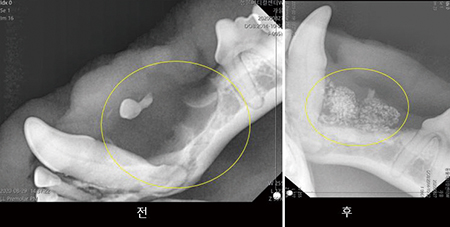

1) GBR의 적용증례

▷ 가을이(4살 시츄, 3.8kg)

- 양측성이긴 하나, ll PM 1~3에 문제 집중 발생

- 골밀도 저하, 치주낭종 발생

- GTR/GBR 진행(2020. 08. 29)

술 후 6개월 재진

- 낭종부위 녹은 뼈의 재생이 보임[fig 06]